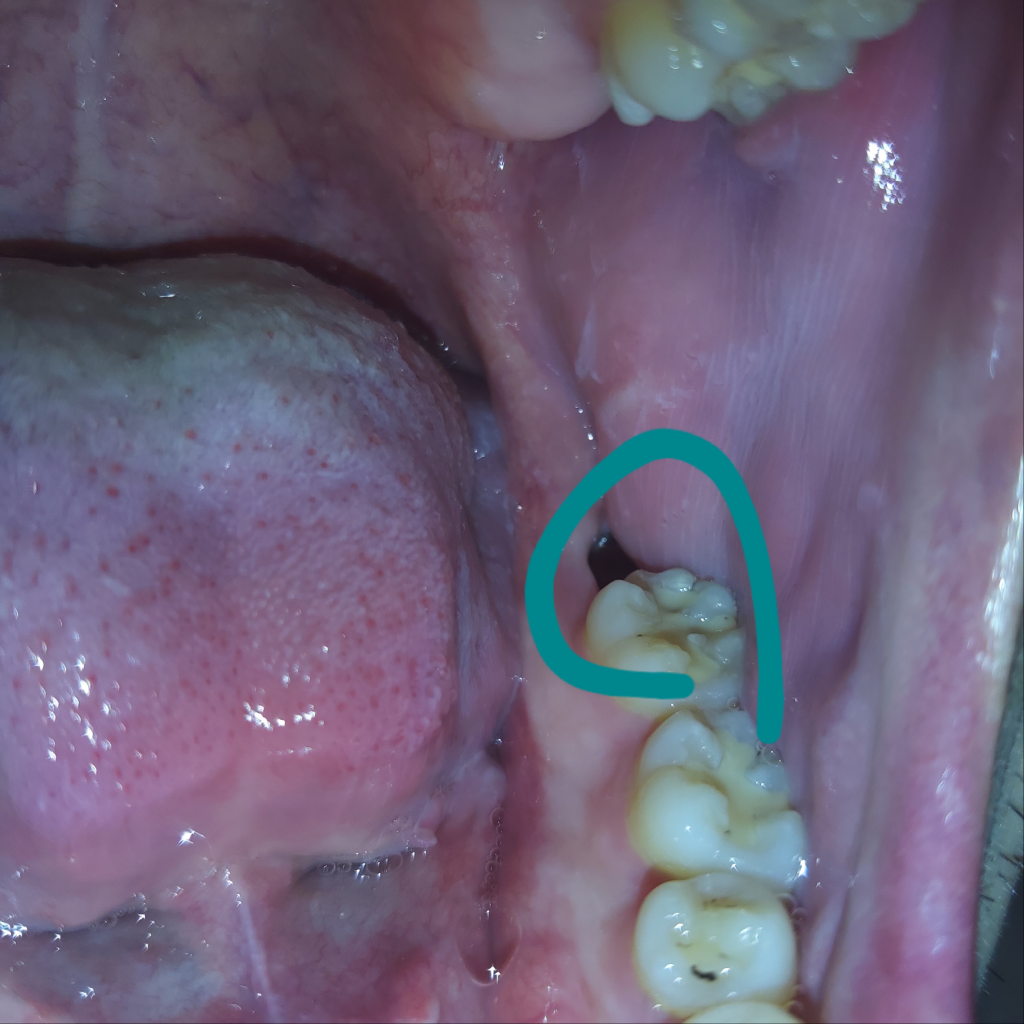

사랑니 발치 후 딱 2주 경과된 매복사랑니 부윈데, 잘 치유되고 있는건가요?

아래 매복 사랑니 발치 후 정확하게 2주가 지나는 중입니다.

아직까지도 붉은 기가 많아 보여 혹 더디게 낫고 있는지 궁금하여 질문드립니다!

• 1번 째 사진

사진상으로는 아무런 문제가 보이지 않습니다.

별 이상없이 잘 낫고 계신것으로 보입니다.

발치후에 혈병형성이 잘 안되어 치유가 늦어지고 있는것으로 보입니다.

안에 이물질이 들어가지 않게 하면서 좀더 시간이 지나면 잇몸이 차오르게 됩니다.

2주 정도지낫다면 아직 상처가 아물때가 아닙니다. 상처가 완전히 아물려면 최소 한두달은 지나셔야됩니다.